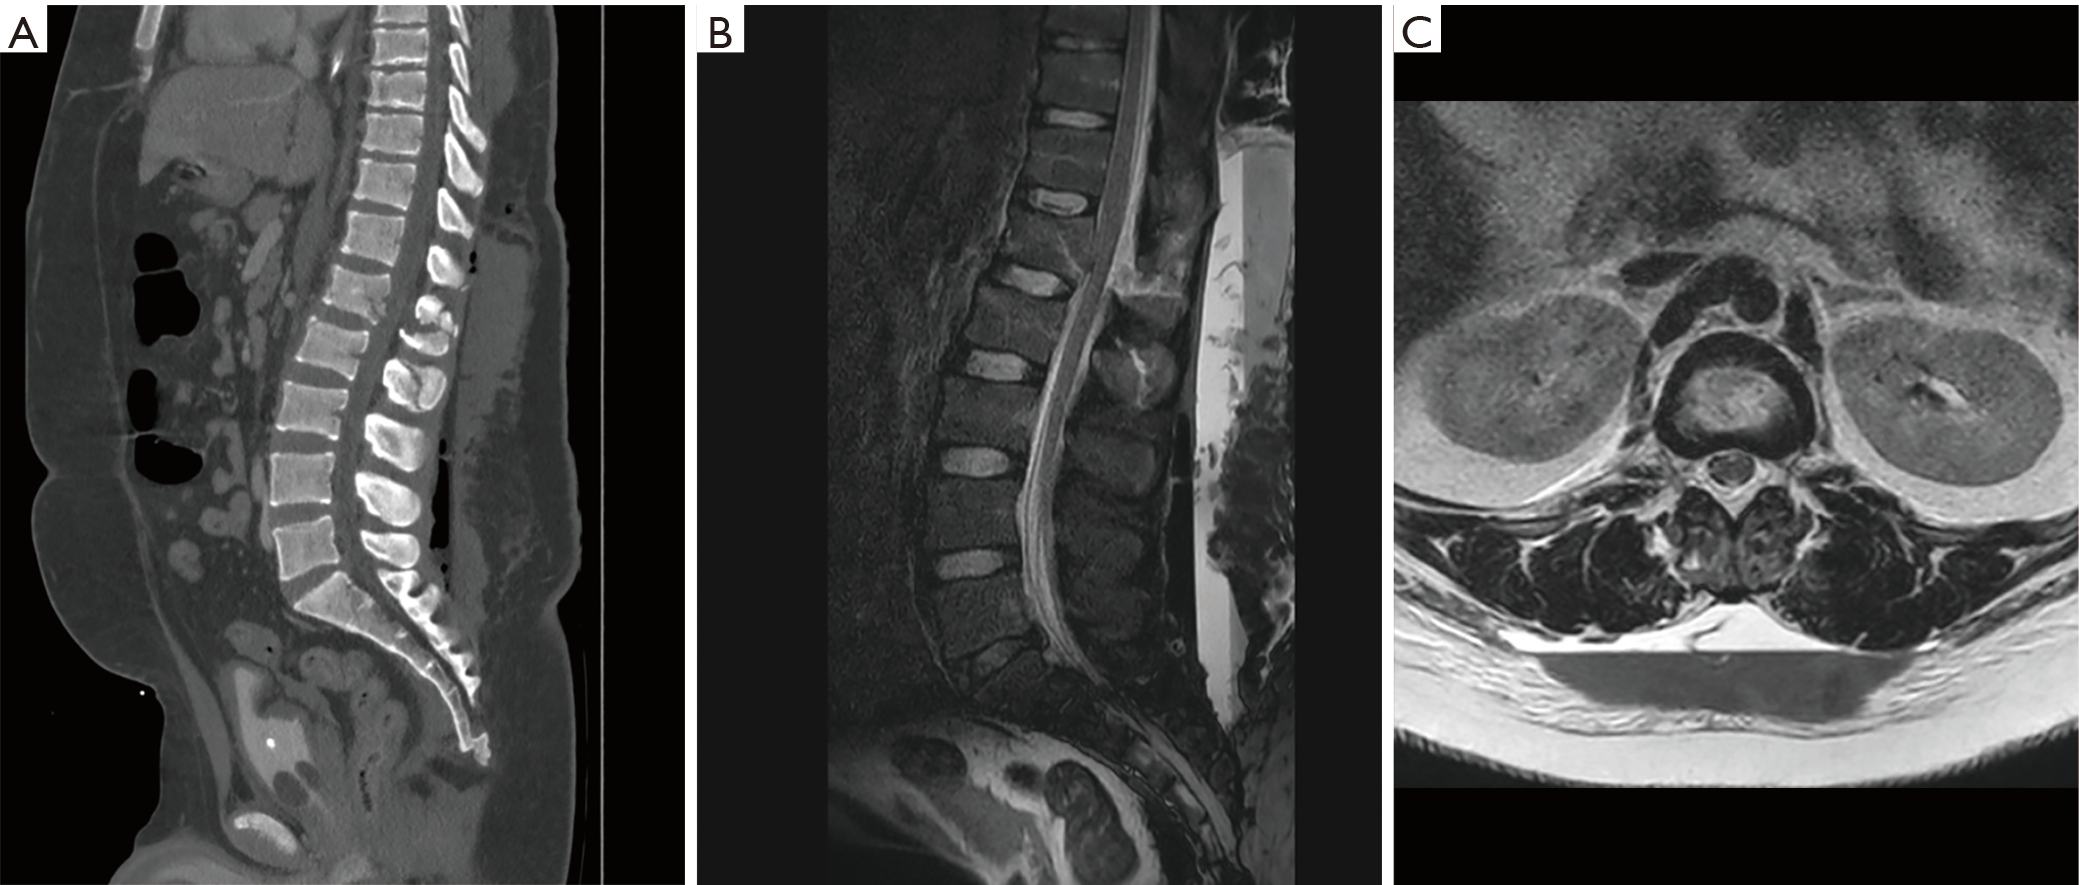

The MorelLavallée lesion in thoracolumbar spine trauma—two index cases Morel Lavallee Lesion Back morel‐lavallée lesion is a closed soft tissue degloving injury usually associated with high‐velocity trauma. That usually occurs after blunt trauma[1][2][3][5]. 1 the injury is characterized by the separation of the. Morel Lavallee Lesion Back.

Figure 2 from MorelLavallée lesion of the lumbar region. Semantic Morel Lavallee Lesion Back 1 the injury is characterized by the separation of the. That usually occurs after blunt trauma[1][2][3][5]. morel‐lavallée lesion is a closed soft tissue degloving injury usually associated with high‐velocity trauma. Morel Lavallee Lesion Back.

(PDF) MorelLavallée Lesion as a Rare Complication of Lumbar Trauma Morel Lavallee Lesion Back morel‐lavallée lesion is a closed soft tissue degloving injury usually associated with high‐velocity trauma. That usually occurs after blunt trauma[1][2][3][5]. 1 the injury is characterized by the separation of the. Morel Lavallee Lesion Back.

(PDF) Pediatric Lumbosacral MorelLavallée Lesion Morel Lavallee Lesion Back morel‐lavallée lesion is a closed soft tissue degloving injury usually associated with high‐velocity trauma. That usually occurs after blunt trauma[1][2][3][5]. 1 the injury is characterized by the separation of the. Morel Lavallee Lesion Back.